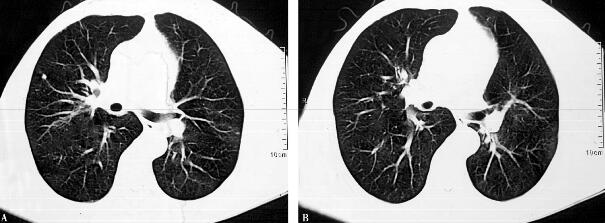

4.胸部CT:双肺多发浸润影,可见少许结节影(图1)。

图1